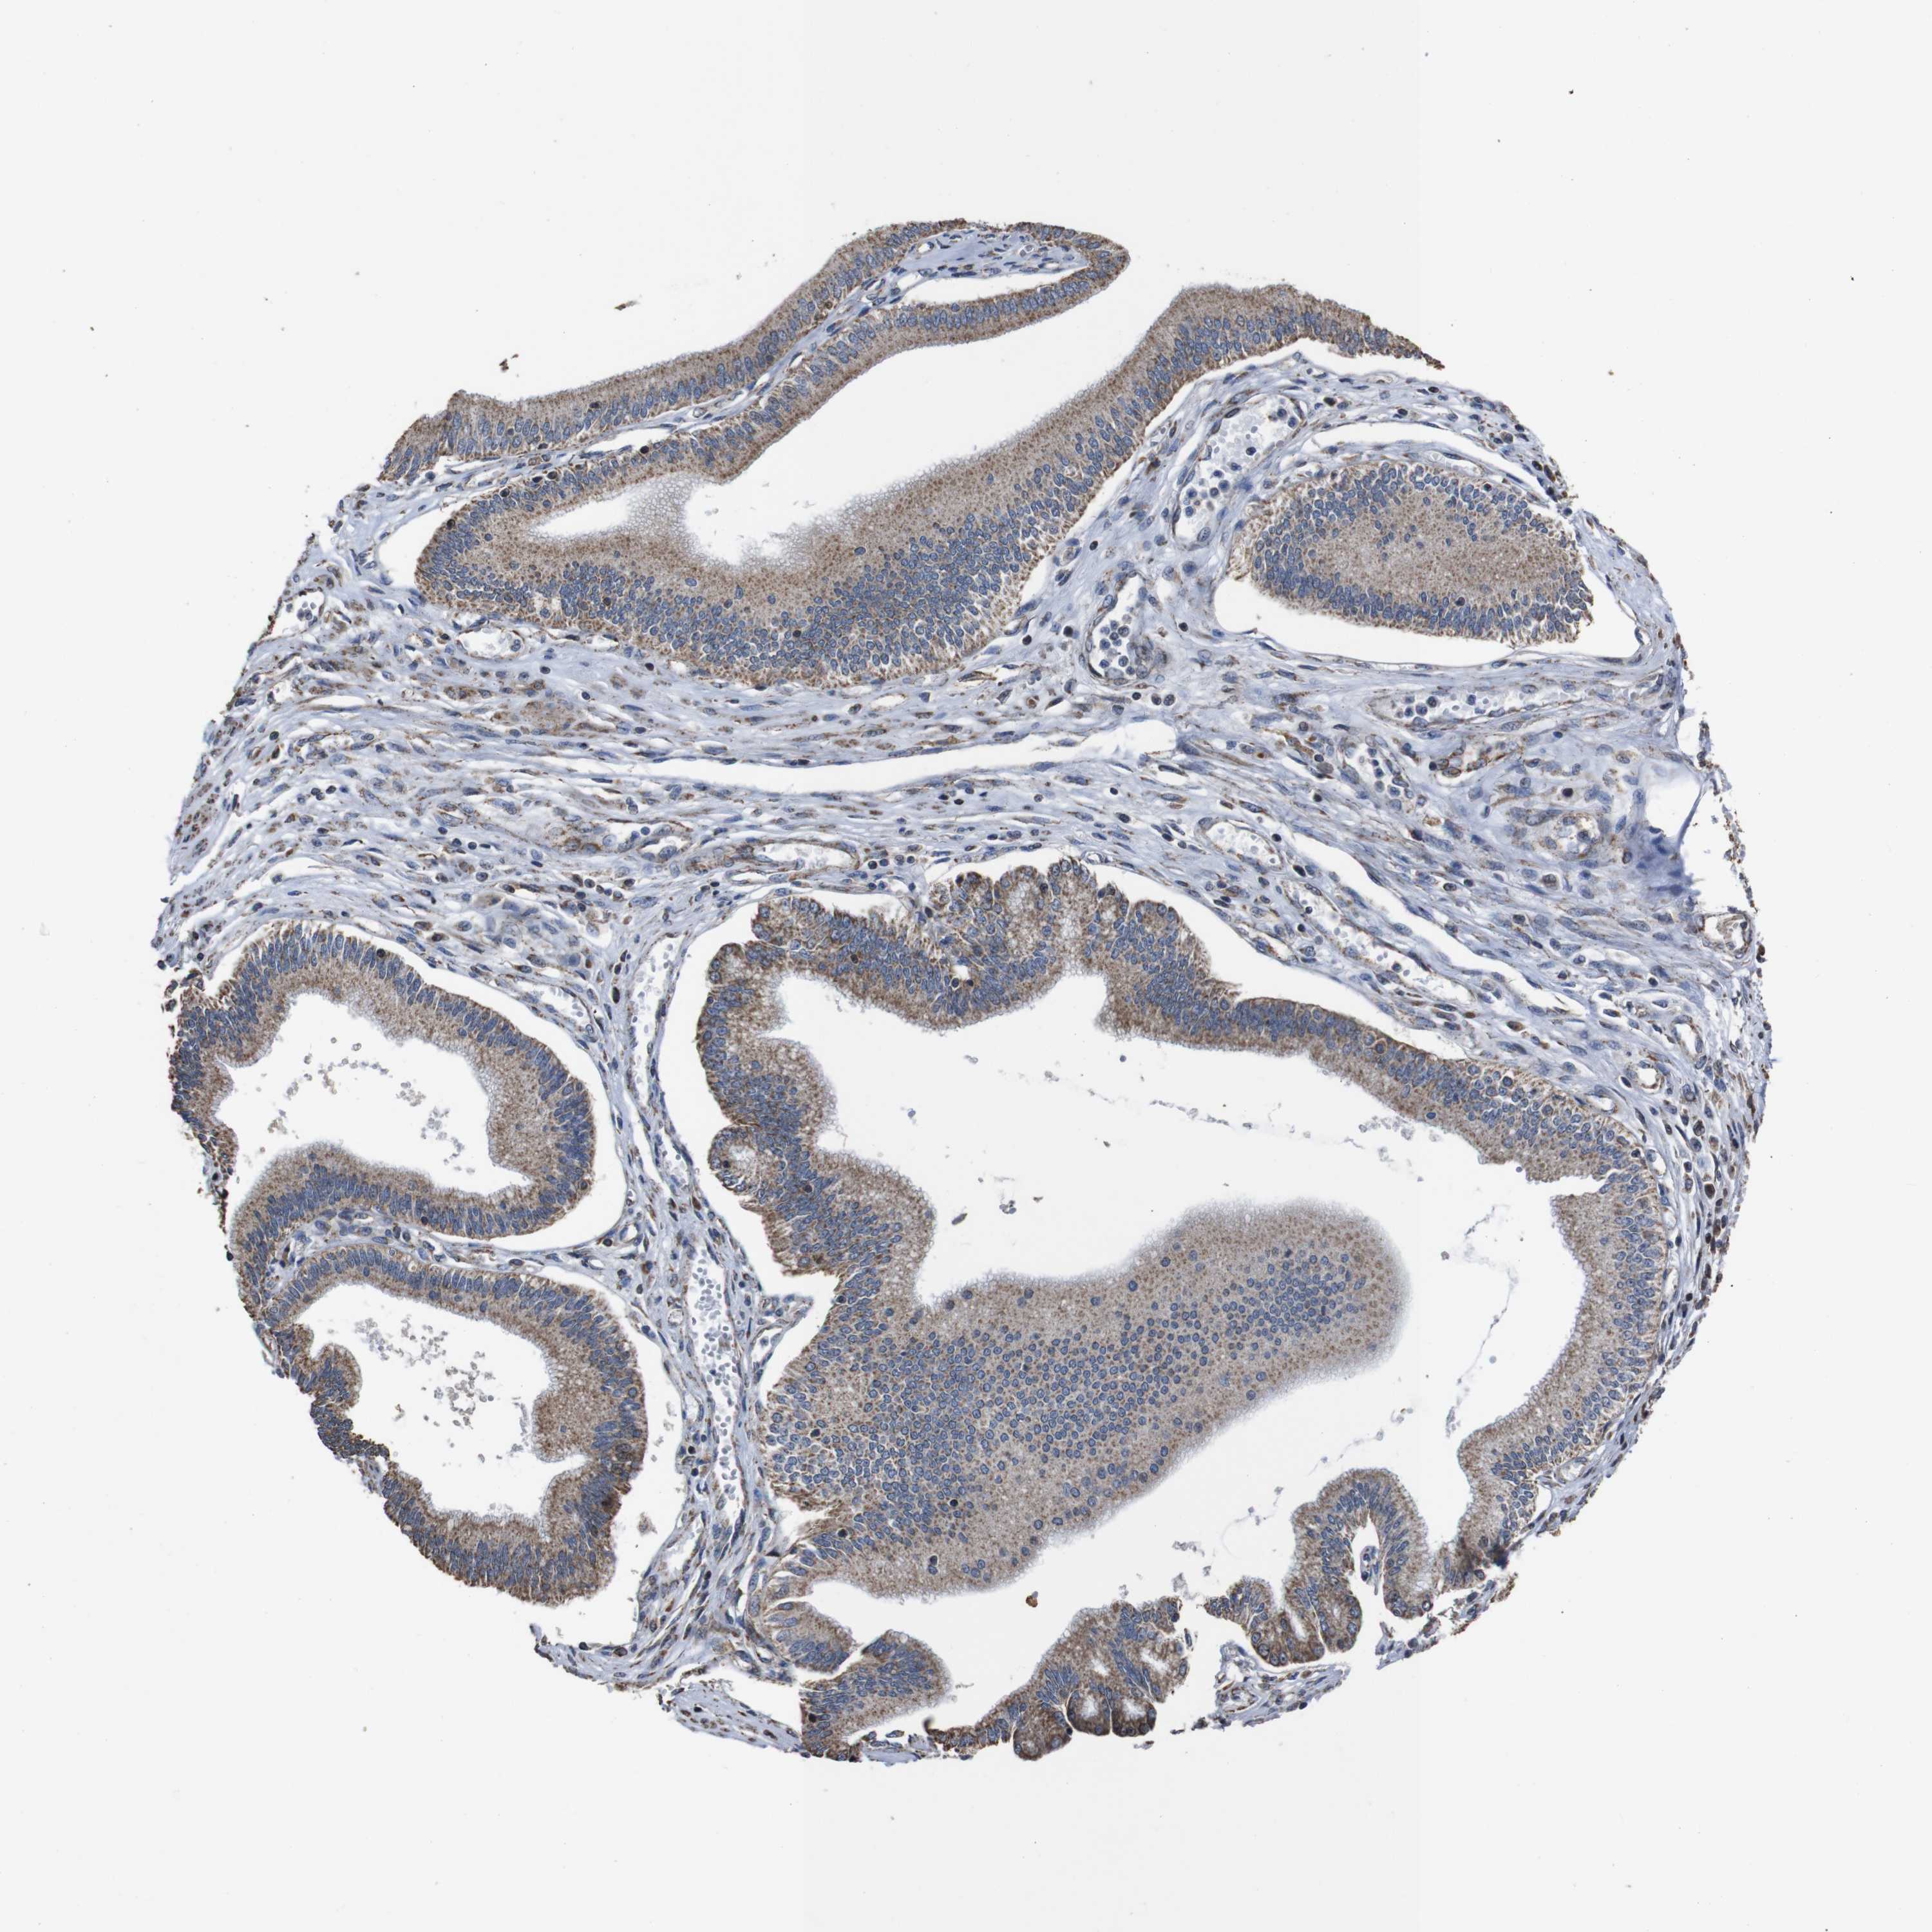

PANCREATIC CANCER - Protein expressioni

A mouse-over function shows sample information and annotation data. Click on an image to view it in a full screen mode. Samples can be filtered based on level of antibody staining by selecting one or several of the following categories: high, medium, low and not detected. The assay and annotation is described here.

Note that samples used for immunohistochemistry by the Human Protein Atlas do not correspond to samples in the TCGA dataset.

Antibody stainingi

Antibody staining in the annotated cell types in the current human tissue is reported as not detected, low, medium, or high, based on conventional immunohistochemistry profiling in selected tissues. This score is based on the combination of the staining intensity and fraction of stained cells.

Each image is clickable and will lead to virtual microscopy that enables deeper exploration of all samples and also displays staining intensity scores, fraction scores and subcellular localization as well as patient and tissue information for each sample.

Antibody HPA011055

Staining

High

Medium

Low

Not detected

Intensity

Strong

Moderate

Weak

Negative

Quantity

>75%

75%-25%

<25%

None

Location

Nuclear

Cytoplasmic/membranous

Cytoplasmic/membranous,nuclear

Adenocarcinoma, NOS